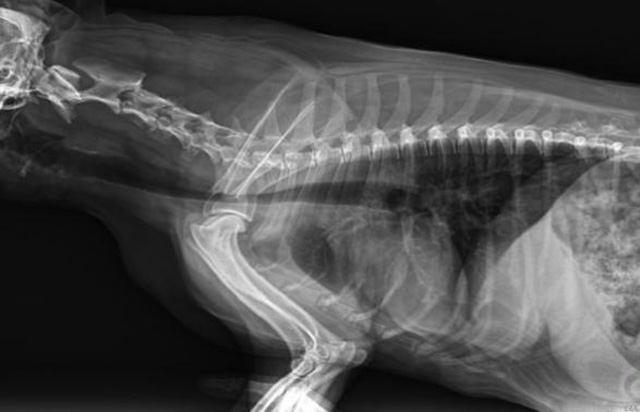

寵物DR是動物專用的數字化攝影系統,x線的穿透能力、低的輻射劑量,輻射劑量比X光低:熒光作用和感光作用,可以穿透動物身體的結構顯示成像,動物的各個部位成像輔助獸醫診療。寵物DR采集時間10ms以下,成像時間僅為3秒,從檢查到出診斷報告大約5—10分鐘。較高的空間分辨力和低噪聲率,可獲得高清晰圖像。 DR成像數字化處理的特點可進行后處理。提高了病灶的檢出率,這樣大大提高檢查的準確率提高診斷準確率避免漏診誤診等情況。

容易引起寵物DR拍攝模糊的原因,DR的參數值及使用過程的設置,還有拍照的條件存在曝光不足和曝光過度的現象;曝光時間的問題,曝光時間太長會導致運動偽影,這個問題也是要避免跟注意。還有就是本身動物的問題,動物不配合亂動,肥胖情緒波動等也會造成DR拍攝的問題影響。過度運動,容易產生圖像模糊或者偽影的情況。